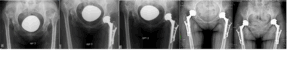

Для хирургического лечения диспластического коксартроза IV типа по Crowe разработан усовершенствованный деротационный имплантат, предназначенный для фиксации зоны подвертельной остеотомии. Биомеханические расчёты подтвердили прочностную надёжность конструкции, а первые операции продемонстрировали её высокую эффективность в стабилизации костных фрагментов при сложной анатомии. На данный момент ведётся клиническая апробация.

Строение стабилизирующей пластины для остеосинтеза зоны остеотомии при диспластических коксартрозах IV типа по Crowe